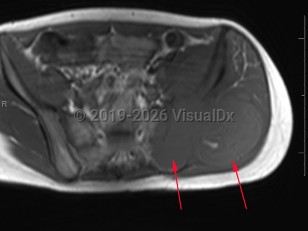

Ewing sarcoma in Adult

Ewing sarcoma is a small, round, blue cell tumor that primarily affects bone and soft tissue. It is often metastatic and has been found in a variety of organs. It typically presents with bone or soft tissue pain. Ewing sarcoma most commonly affects adolescent males. It is considered a poorly-differentiated malignancy on the primitive neuroectodermal tumor (PNET) spectrum. Ewing sarcoma is categorized as a "small round blue cell tumor" due to its histologic appearance, which it shares with other types of malignancies. Ewing sarcomas may be differentiated from these other tumors by CD99 positivity, presence of rosettes on microscopy, and a t(11;22) translocation, which nearly all Ewing sarcomas contain.